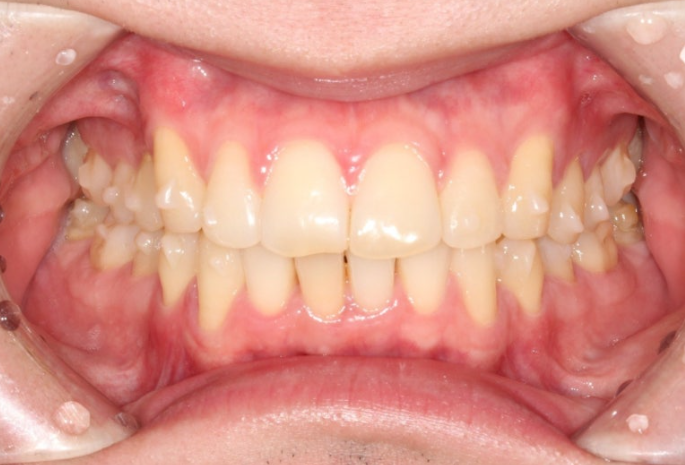

중심선은 맞아졌으며

어금니 교합은 1급 교합관계를 보입니다.

앞니 뻗침은 좋아졌네요.